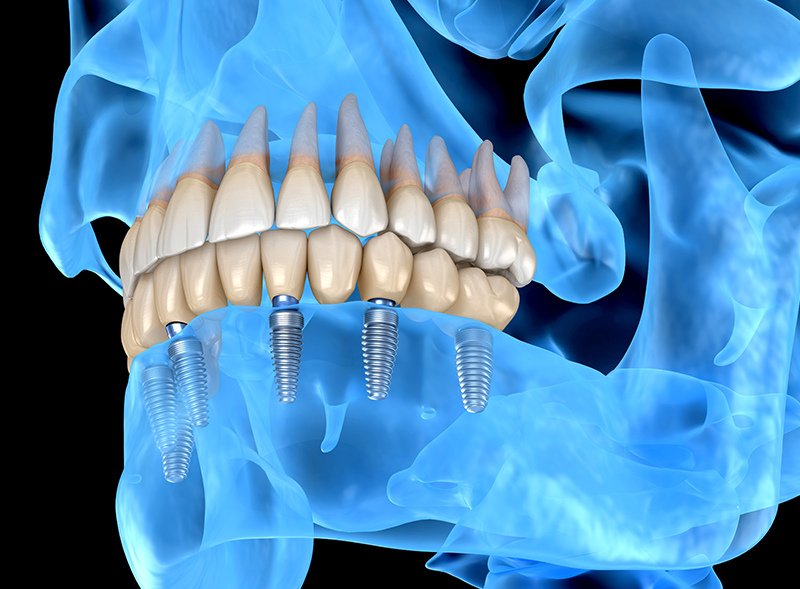

L’implantologia orale è quella branca dell’odontoiatria che permette al paziente affetto da perdita totale o parziale di elementi dentari l’applicazione di protesi fisse con interventi di minima invasività, garantendo ottimo valore sia estetico che funzionale.

La terapia implantare è un procedimento odontoiatrico avanzato finalizzato a sostituire uno o più denti mancanti utilizzando impianti dentali. Gli impianti dentali sono strutture in titanio o leghe biocompatibili che vengono posizionate nell’osso mascellare, svolgendo il ruolo delle radici dei denti naturali. Questo trattamento è una soluzione efficace per ripristinare la funzione masticatoria, l’estetica del sorriso e mantenere la salute dell’osso mascellare. Ecco in cosa consiste la terapia implantare:

- Intervento Chirurgico: Durante l’intervento chirurgico, l’implantologo posiziona gli impianti dentali nell’osso mascellare. Questo può essere eseguito con anestesia locale o sedazione, a seconda delle necessità del paziente.

- Fase di Guarigione: Dopo l’inserimento, inizia la fase di guarigione nota come “osseointegrazione”, durante la quale gli impianti si integrano saldamente nell’osso circostante.

- Protesi Dentaria Completa: Gli impianti possono essere utilizzati per ancorare protesi complete (arcate superiori o inferiori), offrendo una soluzione più stabile rispetto alle protesi mobili tradizionali.

L’implantologia a carico immediato è una procedura innovativa che consente la fissazione di impianti dentali e la posa di protesi nello stesso giorno dell’intervento chirurgico. Questo approccio accelera notevolmente il processo di riabilitazione, offrendo ai pazienti la possibilità di usufruire di denti fissi immediatamente dopo l’implantazione.

Durante la procedura, l’implantologo posiziona gli impianti dentali e attacca una protesi temporanea nella stessa sessione. Questo metodo riduce il periodo di attesa tra l’intervento e il ripristino funzionale, permettendo ai pazienti di godere rapidamente dei benefici estetici e funzionali degli impianti dentali.

L’obiettivo primario di qualsiasi tipo di impianto è raggiungere la completa “osteointegrazione”, che rappresenta la fusione ottimale tra l’osso circostante e l’impianto stesso attraverso la generazione di nuovo tessuto osseo. Solo quando si verifica questa condizione, l’impianto può avere successo diventando una base stabile per la futura protesi artificiale. Questo processo consente all’impianto di sopportare senza problemi le forze generate durante la masticazione, assicurando un’ancoraggio affidabile e duraturo per la protesi dentale.